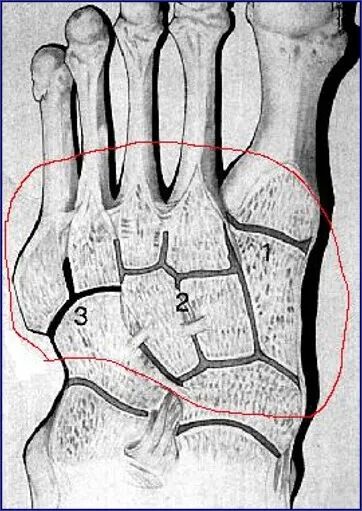

整个关节结构可以划分为三个柱:

• 内侧柱:第一跖骨和内侧楔骨

• 中柱:第2、3跖骨和中外侧楔骨

• 外侧柱:第4、5跖骨和骰骨

第二跖骨基底部深入到3个楔骨形成的马蹄形凹槽中,在跖跗关节的稳定性中起重要作用。

跖骨的基底及楔骨、骰骨形成一拱形结构,也有较好的稳定作用。

在足正位X线上,第1、2、3跖骨的内外侧缘分别和它相对应的楔骨的内外侧缘呈一直线排列;第一、二跖骨基底间隙和内中楔骨间隙相等。

30°斜位上:1、第四跖骨内侧缘和骰骨内侧缘连续成一条直线2、第三跖骨内侧缘和外侧楔骨内侧缘连续成一条直线3、第二、三跖骨基底间隙和内、中楔骨间隙相等。